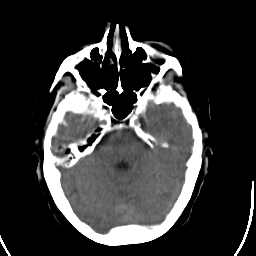

Stroke CT #1 -- Slice #7

[Home][Help][Clinical] Slice 7